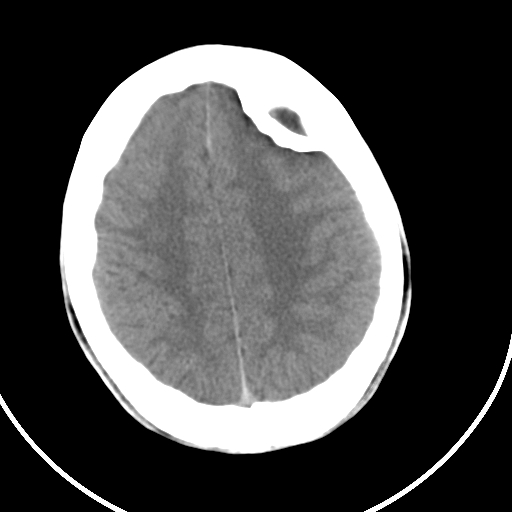

标题: CT21939:男20岁,外伤一年后,现头疼. [打印本页]

标题: CT21939:男20岁,外伤一年后,现头疼.

左侧额部硬膜外血肿机化、骨化。

左侧额部硬膜外血肿机化、骨化